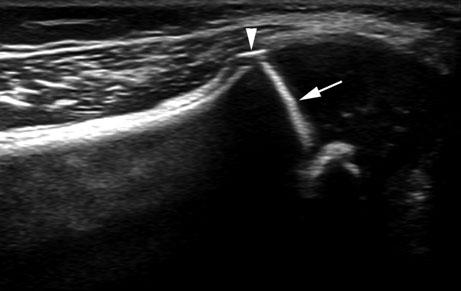

Fig. 2.4 Ultrasound imaging also clearly demonstrates bone bark at the metaphyseal collar (arrowhead) and the zone of provisional calcification (arrow) in a 7-month-old infant